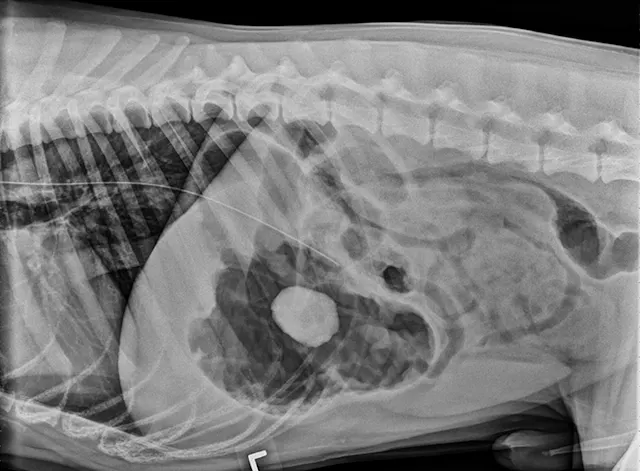

FIGURE 1A

Lateral view. Abdominal radiographs showing a rock foreign body that appears to be located in the small intestine. No small intestinal foreign body could be located on abdominal ultrasound; however, a shadowing foreign object was possibly located in the stomach.